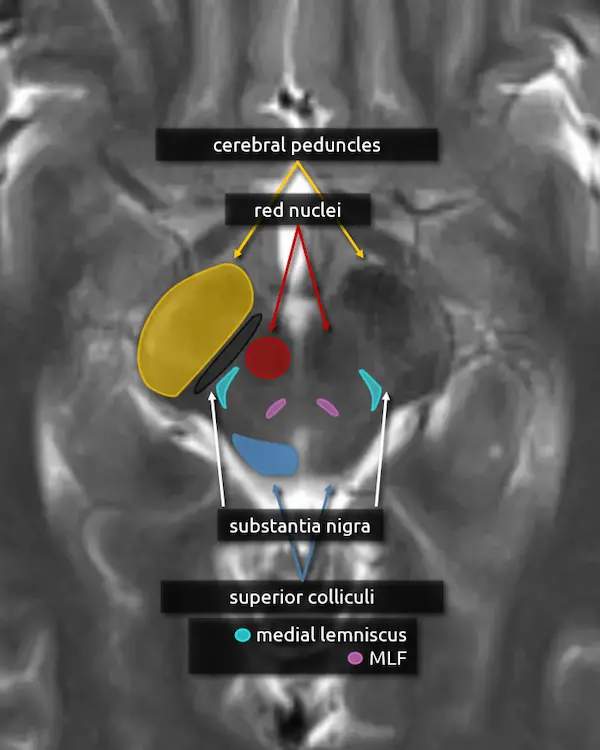

1. Cerebral peduncles

2. Superior colliculi

3. Red nucleus

The red nucleus is a component of the extrapyramidal motor system. It takes input from the cerebellum (via the superior cerebellar peduncles), motor, premotor, and frontal cortices and projects to the contralateral cervical spinal cord and, to a lesser extent, the ipsilateral inferior olivary nucleus (see rostral medulla below) via the rubrospinal tract. The red nuclei are dark on T2-weighted MRI images, producing the eyes of the "Mickey Mouse" appearance of the upper midbrain.

4. Substantia nigra

The substantia nigra is a large nucleus at the base of the cerebral peduncle that spans the midbrain. It is a major component of the extrapyramidal motor system and has bidirectional connections between the striatum (caudate and putamen), forming the nigrostriatal pathway. It is composed of two areas: the pars compacta and the pars reticulata.

5. Medial lemniscus

The medial lemniscus is an ascending sensory pathway that spans the entire brainstem, originating at the nucleus gracilis and cuneatus (see level 5) in the medulla and ending at the primary sensory nucleus of the thalamus: the ventral posterolateral nucleus (VPL). It begins medially in the medulla and becomes more lateral at the level of the midbrain, located in close proximity to the substantia nigra. It is responsible for vibration sensation, fine touch, and proprioception.

6. Medial longitudinal fasciculus (MLF)

The MLF is an ascending and descending pathway responsible for coordinating eye movements. It connects all of the cranial nerve nuclei that innervate the extraocular muscles (CN III, IV, and VI) as well as the vestibulocochlear nuclei (CN VIII). The MLF spans the entire brainstem, however lesions producing visual symptoms will probably be in the midbrain or pons.